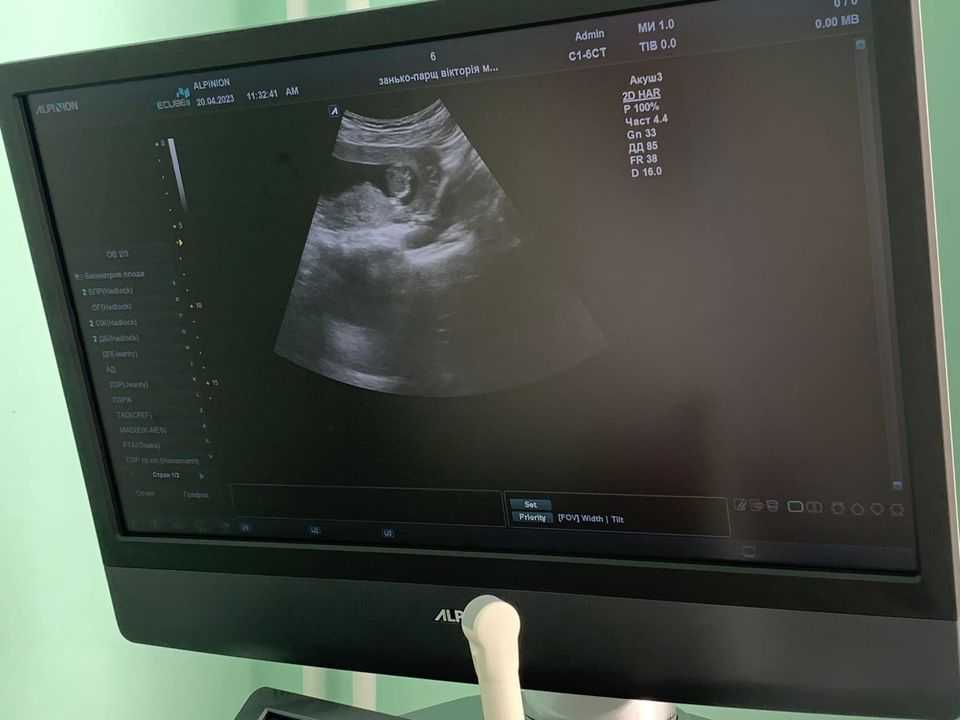

Соснівська міська лікарня отримала сучасний апарат ультразвукового обстеження ECUBE 8 виробництва Кореї, який придбано за кошти міського бюджету.

«За цей тиждень ми провели обстеження вагітних на 1, 2 та 3 триместрі, а також пацієнток з гінекологічними і навіть онкологічними паталогіями. Цей УЗД-апарат цінний для медиків Соснівської міської лікарні та мешканців громади насамперед тим, що має розширені можливості обстеження пацієнтів з різною паталогією і за різних показів.

За перший тиждень лікар-гінеколог Людмила Ярович обстежила 15 вагітних та гінекологічних пацієнток.